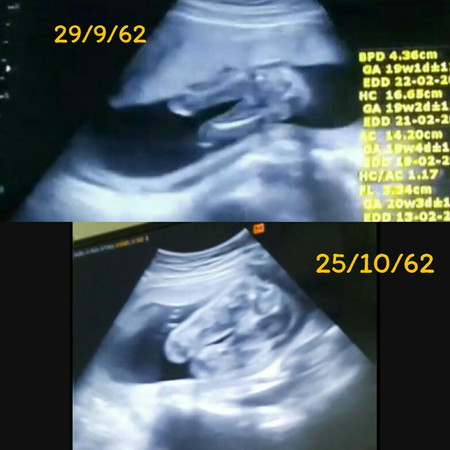

หนูเป็นผู้หญิงค่ะ

จากคราวที่แล้วป้าหมอบอกว่าอาจได้ลูกสาว ตอนนี้ป้าหมอยืนยันแล้วว่าหนูเป็นผู้หญิงค่ะ แม่ๆช่วยแนะนำชื่อลูกสาวหน่อยค่า แม่อยากได้ชื่อที่มี ด.เด็ก เพราะคนโตชื่อชายแดน หลานสาวอีก2คน ชื่อ สุดา กับโมเด็มค่ะ